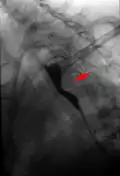

Arteria lusoria in der Schluckuntersuchung: Impression der Speiseröhre von hinten. -

Bandförmige Impression der Speiseröhre durch Arteria lusoria. Darunter (Pfeile) Einengung der Speiseröhre durch einen Tumor, der für die Schluckbeschwerden ursächlich ist. -